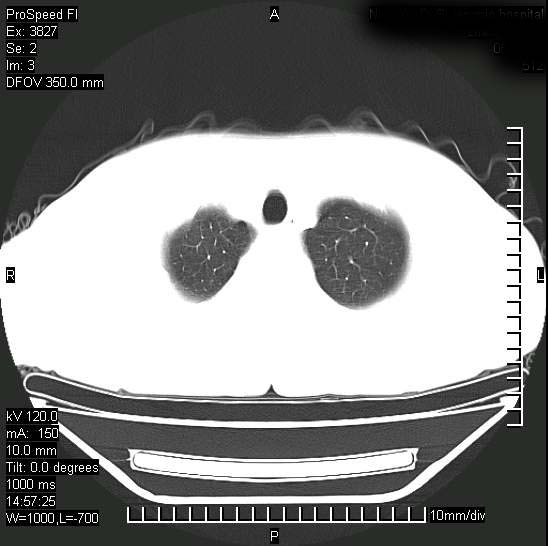

男性,一月前出现右侧肋区疼痛,较剧烈,干咳,无发热,自诉使用抗炎药后缓解,几天前又出现左侧剧烈疼痛,

发热,体温38。9,今天ct,考虑左侧包裹性脓胸,胸腔积液,右上中肺小斑片影,结核/炎症?胸水未见恶性细胞。

支持:脓胸!并双肺继发性肺结核!

脓胸没问题,肺内还可见感染灶,感觉不像是结核性病变.